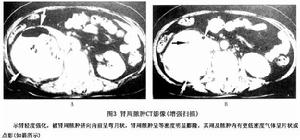

3.CT掃描對腹膜後膿腫的診斷和定位具有極大幫助,其敏感性可達100%,尤其對多發性膿腫的診斷再次手術入路的選擇和手術範圍的確定具有特殊重要的意義。